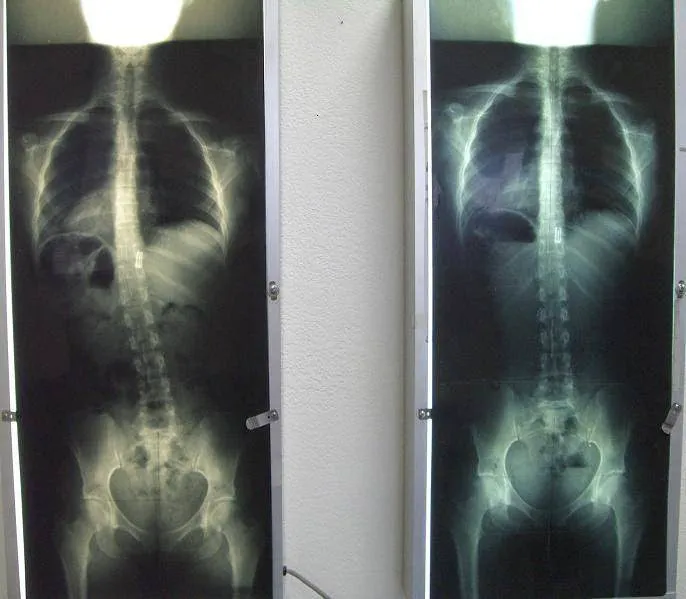

Chiropractic care, at its core, focuses on the diagnosis, treatment, and prevention of mechanical disorders of the musculoskeletal system, particularly the spine, and their impact on nervous system function and overall health. What distinguishes Gonstead Clinics and Dr. Eric Pastrmac is their adherence to the precise and thorough Gonstead System of Chiropractic. This methodical approach involves detailed analysis, including full spine X-rays, static and motion palpation, visualization, and nervoscope readings, to pinpoint the exact location of subluxations (misalignments) in the spine. This precision allows for highly specific and effective adjustments, leading to remarkable patient outcomes. Dr. Pastrmac’s dedication to this meticulous method, combined with his evident skill, has earned him a reputation that extends far beyond Irvine, drawing patients from as far as Los Angeles and beyond.

- Gonstead Spinal Adjustments: The core service, involving detailed analysis using full spine X-rays, nervoscope, palpation, and visualization to identify specific vertebral subluxations. Adjustments are then performed with precision to correct these misalignments, optimizing nervous system function.

- Restoration of Spinal Curvature: Specialized techniques to help restore the natural and healthy curvature of the spine, particularly in the neck (cervical lordosis), which can be crucial for long-term relief from tension and pain.

- Specific Vertebral Correction: Focus on correcting specific misalignments, such as those in the C1, C2, and C4 vertebrae, as highlighted by patient testimonials, which can have profound effects on overall well-being and nerve function.

- Restoration of Neck Curvature and Specific Corrections: A notable highlight is Dr. Pastrmac's success in restoring the natural curvature of the neck and correcting specific, difficult-to-adjust vertebrae like C1, C2, and C4, leading to profound improvements in patient health.

Nov 16, 2021 · susan marozikDr. Pastrmac was able to relieve almost a decade of tension and stress in my neck and back. After my first visit I already noticed a huge difference. He fixed my C1, C2, & C4, and over subsequent visits was also able to restore the curvature in my neck. Years of tension and soreness in my shoulders as well as the tightness in my chest are gone. His work is amazing; I was initially scared to get adjusted, but he put me at ease. I highly recommend him.

Apr 21, 2023 · bela aI’m so glad to have found Dr. P! I’ve been to several different chiropractors before him but never got long term results. I’ve been going to Dr. Pastrmac’s for about a month now and I’ve noticed my lingering hip pin that no one else could correct nearly gone. He’s thorough and always checks my X-rays before each adjustment. Definitely excited to see the changes to come in the following months and being pain free!